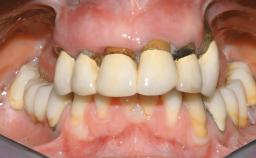

Immediate Loading of Eight Implants in the Maxilla and Six Implants in the Mandible and Final Restoration with Three-Unit and Four-Unit FDPs

Prosthesis Type FDP

SAC Level Complex

Defining Characteristics Fully edentulous upper jaw to be rehabilitated with an implant-borne fixed dental prosthesis

Occlusal Scheme/Issues Anterior guidance